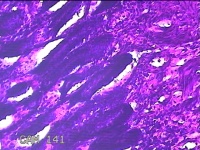

阑尾

性别

男

年龄

32岁

临床诊断

1.急性化脓性阑尾炎并穿孔 2.弥漫性腹膜炎

一般病史

转移性右下腹疼痛1天。

标本名称

大体所见

灰白暗红色阑尾4.8x1.3x0.7cm一条,表面糜烂,肿胀,带少许系膜,切断阑尾,见腔内暗红色。

这个片子没法诊断,需要改进。